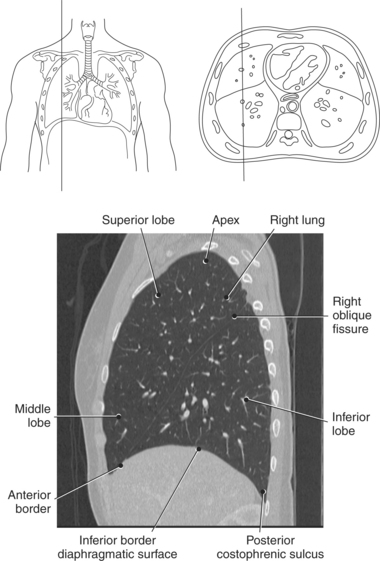

The lungs are the organs of respiration, where gaseous exchange occurs between the respiratory air and blood. They are composed of a spongelike material, the parenchyma, and surrounded by a layer of serous membrane. The large conical-shaped lungs extend up to or slightly above the level of the first rib at their apex and down to the dome of the diaphragm at their wide concave-shaped bases or diaphragmatic surfaces (Figure 6.9). Each lung has a mediastinal or medial surface that is apposed to the mediastinum, and a costal surface that is apposed to the inner surface of the rib cage. Each lung also has an inferior, anterior, and posterior border. The inferior border extends into the costodiaphragmatic recess of the pleural cavity, and the anterior border of each lung extends into the costomediastinal recess of the pleural cavity (Figure 6.10). Two prominent angles can be identified at the medial and lateral edges of the lung bases. The medial angle is termed the cardiophrenic sulcus, and the lateral angle is termed the costophrenic sulcus (Figure 6.11 and 6.12). The lungs are divided into lobes by fissures that are lined by pleura and may extend as far as the hilum (Figure 6.13). The right lung has three lobes (superior [upper], middle, and inferior [lower]), whereas the left lung has just superior (upper) and inferior (lower) lobes (Figures 6.6 and 6.11 through 6.13). The inferior lobe of the right lung is separated from the middle and superior lobes by the oblique fissure, termed oblique because of its posterosuperior to anteroinferior course. Separating the middle lobe from the superior lobe is the horizontal fissure (Figures 6.9 and 6.14, A). An oblique fissure also separates the superior and inferior lobes of the left lung (Figure 6.11). The left lung has a large notch on the medial surface of its superior lobe called the cardiac notch and a tonguelike projection off its inferoanterior surface termed the lingula. Each lung has an opening on the medial surface termed the hilum (Figures 6.14 through 6.16). This opening acts as a passage for mainstem bronchi, blood vessels, lymph vessels, and nerves to enter or leave the lung and is commonly referred to as the root of the lung.